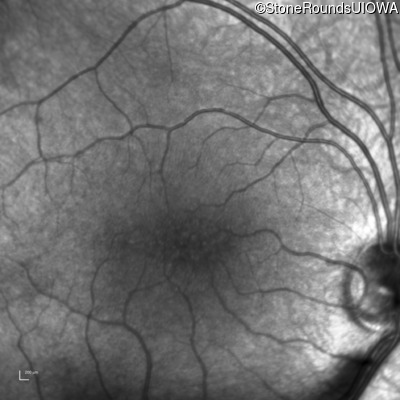

Infrared Fundus Photograph - Right - 20/40 -2

Exemplar